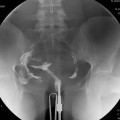

Réaliser un ASP de face stricte et éventuelle rotation pour être dans le plan de l’utérus.